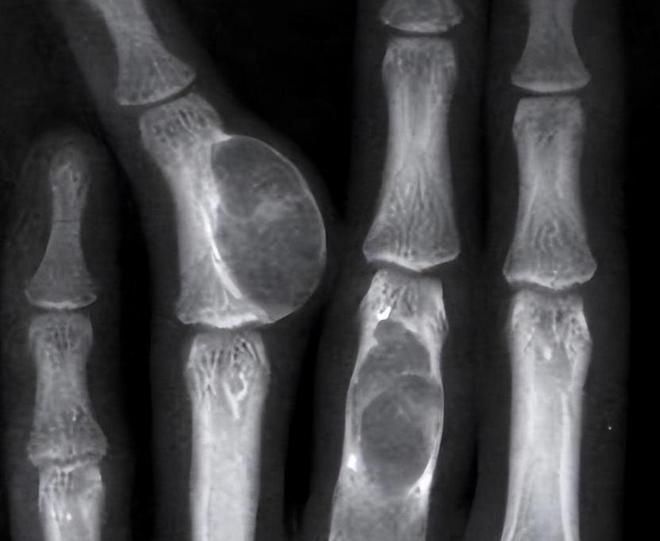

医生告诉她们,治疗的唯一办法就是化疗配合手术,但即使如此,李明馨的生命可能也只剩下五年。

但医生告诉她,情况已经不容乐观,再拖延只会让癌细胞进一步扩散,手术是目前唯一的出路。